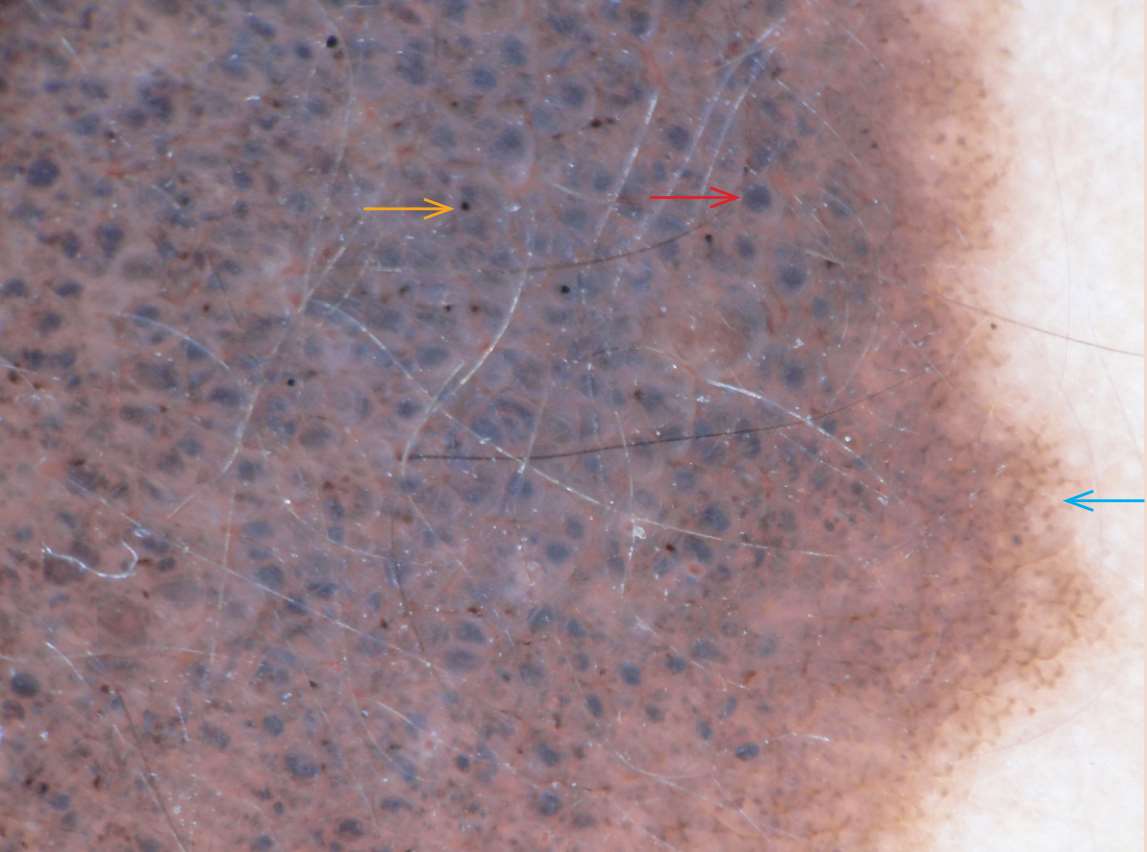

斑点(dots)是指直径<0.1mm的圆形结构(图1-3),根据颜色可以分为黑斑点、褐色斑点、灰斑点、蓝灰斑点、蓝斑点。黑斑点主要是由角质层和表皮上部游离的黑色素积聚而成。褐色斑点是由真皮与表皮交界处的黑素颗粒聚集而成。蓝灰斑点是由真皮乳头细小色素结构构成。蓝灰斑点或蓝斑点是由噬黑素细胞中散在的细小稀疏色素颗粒或真皮乳头或网状层游离的色素颗粒组成。不伴色素网的弥漫性蓝灰斑点常见于慢性苔藓样角化病,簇集的褐色斑点见于黑素瘤,良性皮损的中央常有黑斑点。

图1-3 中央可见大量的蓝灰色小球( ↑ )和少量黑斑点( ↑ ),边缘可见断裂的色素网( ↑ )

小球(globules)是指对称的、圆形或椭圆形、边界清楚的结构(图1-3),可以是褐色、黑色、红色,直径通常>0.1mm。褐色、黑色小球对应于真皮与表皮交界处或真皮乳头的良性和恶性黑素细胞巢、色素团块或噬色素巨噬细胞。褐色小球对应于位于真表皮交界处的黑素细胞巢。

分枝条纹(branched streaks)是指断裂的色素网状结构,是色素网破坏后的残留结构(图1-3),组织学上对应于表皮嵴残留的色素和真皮乳头内的黑素细胞桥接巢。